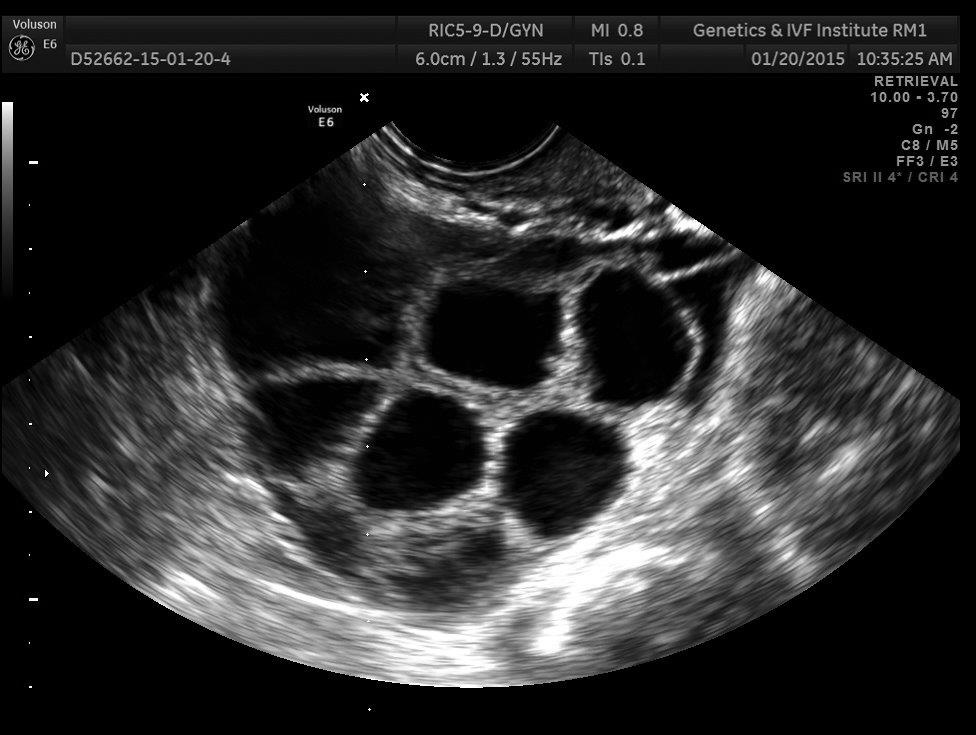

Lesson 6: Ovaries go from walnut- to orange-sized

I knew my ovaries would get larger, but I couldn’t easily find good data about exactly how large we’re talking.

My current understanding is that ovaries are usually the size of a walnut, and when stimulated they each become the size of a small orange:

By day 5 of the stimulating hormones, I could feel where exactly my ovaries were located in my groin area - a strange sensation! On day 7 and 8, it was noticeably uncomfortable to walk: I felt a sensation like tugging on supporting ligaments.